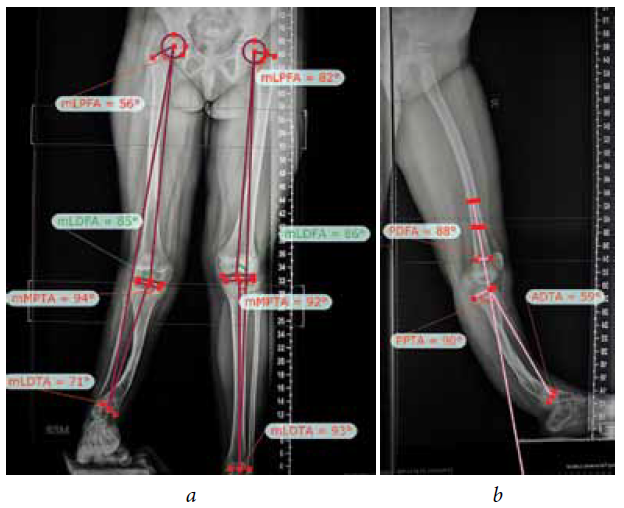

The second stage of treatment was the recommended correction of the resulting multiplane deformities of the affected lower extremity (mMPTA was 94°, mLDTA was 71°, aPPTA was 90°, and aADTA was 59°, shortening the affected lower limb by 8.0 cm). For lengthening and deformity correction of the right lower limb, the patient underwent preoperative planning for deformity correction with the exception of osteotomies in the area of consolidated pseudoarthrosis at the age of 9 years. According to the plan, a two-level osteotomy of the shin bones was performed, as along with lengthening by 5 cm by the Ilizarov method. The deformity was corrected using a repositional unit with Ortho-SUV computer navigation properties. The period of deformity correction was 58 days, and the external fixation period was 247 days. At the end of the fixation period, a recurrence of deformities of the tibial bones was detected with the formation of a deformity apex at the level of the proximal and distal tibial growth zones (mMPTA was 94°, mLDTA was 82°, aPPTA was 86°, and aADTA was 80°) (Fig. 1–4). We applied hemiepiphysiodesis to correct the recurrence of valgus deformity of the tibia. The period of deformity correction was 269 days. The reference angles values of the tibia were within the accepted ranges.

Fig. 2. Radiographs of the patient with cCPASB prior to deformity correction: а — anterior-posterior view; b — lateral view

Fig. 3. Preoperative planning for deformity correction in a patient with cCPASB using specialized software: а — anterior-posterior view; b — lateral view